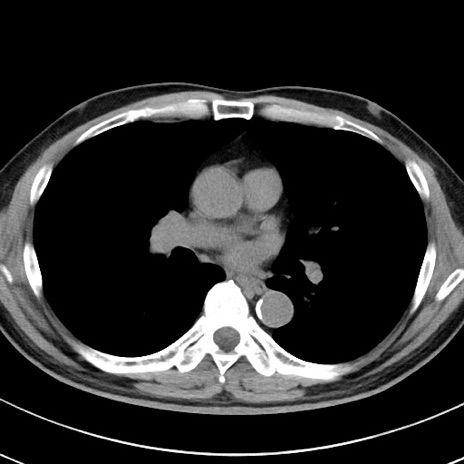

【腹部TIPS】症例29 参考症例 CT(横断像)

症例

70歳代男性